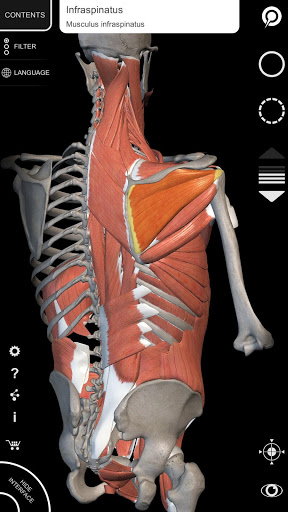

Завдяки простому та інтуїтивно зрозумілому інтерфейсу можна спостерігати кожну анатомічну структуру під будь-яким кутом.

Поділ за регіонами та попередньо визначені види полегшують спостереження та вивчення окремих частин або груп систем і зв’язків між різними органами.

• Візуалізація м’язів через рівні шарів від поверхневих донизу до найглибших

• Вибравши модель або шпильку, з’явиться відповідний анатомічний термін

• Опис м’язів: походження, приєднання, іннервація та дія